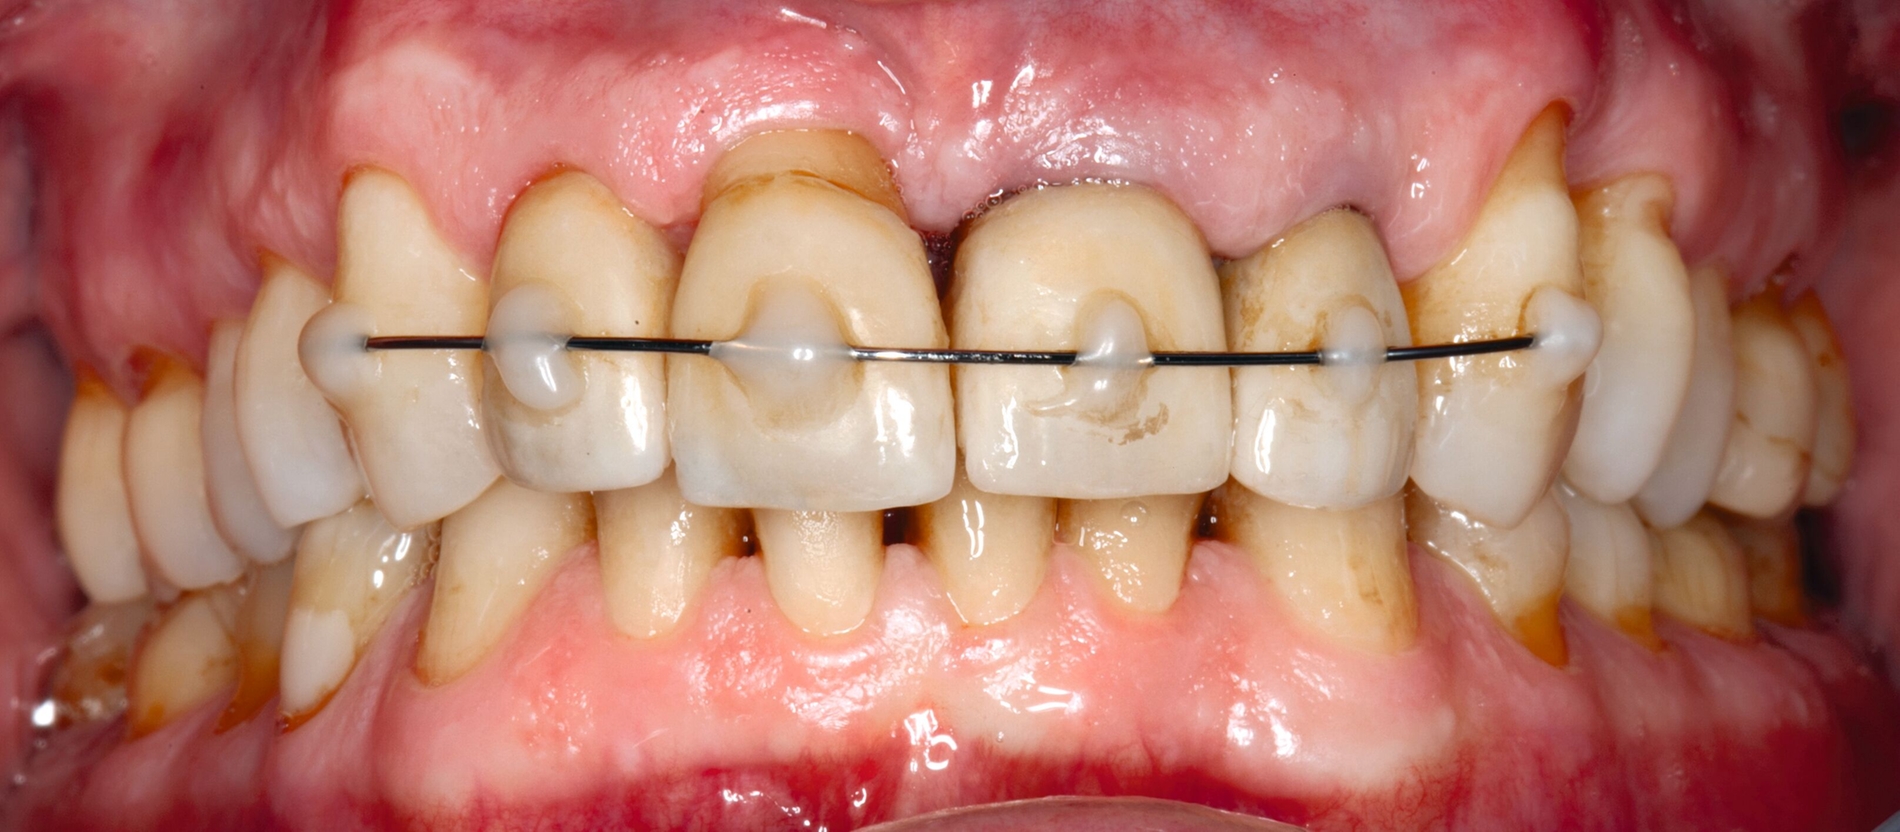

Möglichkeiten zur Therapie des okklusalen Traumas sind das selektive Einschleifen okklusaler Frühkontakte, die Schienung der betroffenen Zähne oder gegebenenfalls auch kieferorthopädische Bewegungen der Zähne sowie eine Kombination der genannten Therapieformen [Fan und Caton, 2018; Dommisch et al., 2022]. Ein Beispiel für eine Schienung bei Vorliegen einer okklusalen Dysfunktion ist in Abbildung 2 dargestellt.